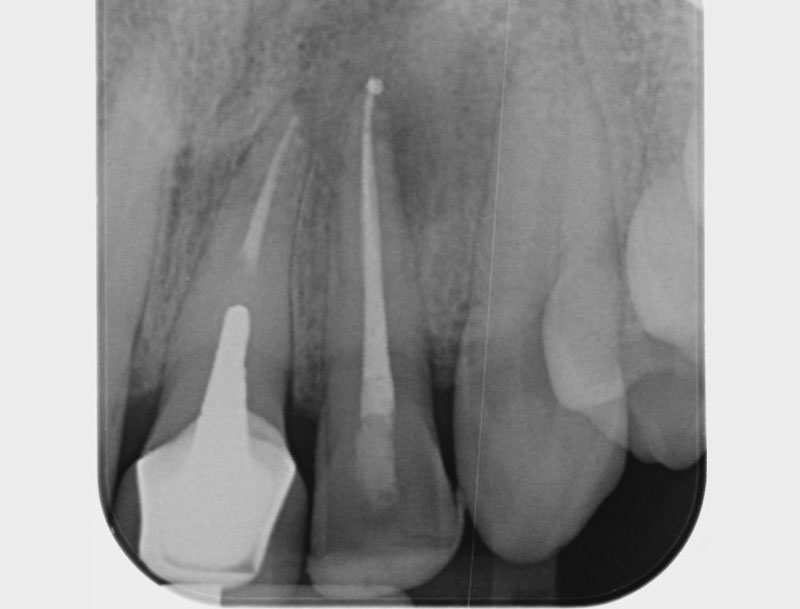

• Traitement endodontique : Sous anesthésie locale et à travers la protection d’un champ opératoire nous accédons à la pulpe de la dent à soigner, puis aux canaux de ses racines que nous devons désinfecter. Ce soin nécessite l’élimination complète de la source de contamination (souvent la carie) parfois sous une ancienne reconstitution ou une couronne qu’il faut alors retirer. Une fois le nettoyage et la mise en forme des canaux réalisés, nous les obturons de façon hermétique avec un ciment et un matériau thermoplastique appelé Gutta Percha. Ceci afin d’empêcher une nouvelle prolifération bactérienne et d’assurer le maintien de la dent dans ses structures de soutien (ligament parodontal et os alvéolaire). L’ouverture effectuée au centre de la dent sera d’abord refermée avec un pansement provisoire avant d’envisager ensemble la reconstitution d’usage : un composite, un inlay-onlay ou une couronne.

Avant

Après